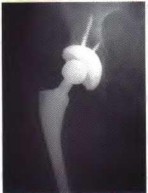

ORTHOPEDIC MCQS 010 Adult Reconstructive Surgery of the Hip and Knee Examination 7 2010 Adult Reconstructive…